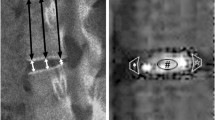

Radiographic analysis of disc height

To assess the height of each disc, lateral radiographs of the lumbar segment were taken just before injection and at 2-week intervals after that until the animals were euthanized. Under general anesthesia, a lateral lumbar radiograph was taken using fluoroscopy. A 10-mm metal wire was placed at the height of the rabbit spine in the lateral recumbent position as a marker for calibration. All radiographic images were independently analyzed using an image analysis software, ImageJ (US National Institutes of Health, Bethesda, MD, USA), by an orthopedic researcher blinded to the treatment groups. The IVD height was measured using the method of Masuda et al. [22], with a modification. Anterior disc height (Ha), middle disc height (Hm), and posterior disc height (Hp) were measured and calibrated (Fig. 2). Disc height (DH) was calculated as follows: (Ha+Hm+Hp) / 3 (Fig. 2). The disc height index (DHI) was defined as: DH (of L1–L2, L2–L3, L3–L4, or L4–L5 discs) / DH of L5–L6 disc (NI control). Change in DHI was expressed as percentage DHI (%DHI) and normalized to the measured baseline DHI: % DHI = (post-injection DHI/baseline DHI) × 100.

Radiographic measurement of disc height. Anterior disc height (Ha), middle disc height (Hm), and posterior disc height (Hp) were measured and calibrated. Disc height (DH) was calculated as (Ha +Hm +Hp) /3. The disc height index (DHI) was defined as: DH (L1–L2, L2–L3, L3–L4, or L4–L5 disc) / DH of L5–L6 disc (non-injection (NI) control). Change in DHI was expressed as percentage DHI (%DHI) and normalized to the measured baseline DHI: % DHI = (post-injection DHI/baseline DHI) × 100